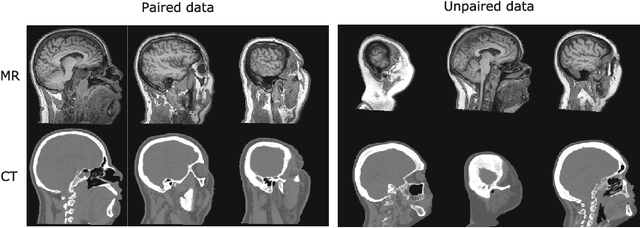

MR-only radiotherapy treatment planning requires accurate MR-to-CT synthesis. Current deep learning methods for MR-to-CT synthesis depend on pairwise aligned MR and CT training images of the same patient. However, misalignment between paired images could lead to errors in synthesized CT images. To overcome this, we propose to train a generative adversarial network (GAN) with unpaired MR and CT images. A GAN consisting of two synthesis convolutional neural networks (CNNs) and two discriminator CNNs was trained with cycle consistency to transform 2D brain MR image slices into 2D brain CT image slices and vice versa. Brain MR and CT images of 24 patients were analyzed. A quantitative evaluation showed that the model was able to synthesize CT images that closely approximate reference CT images, and was able to outperform a GAN model trained with paired MR and CT images.